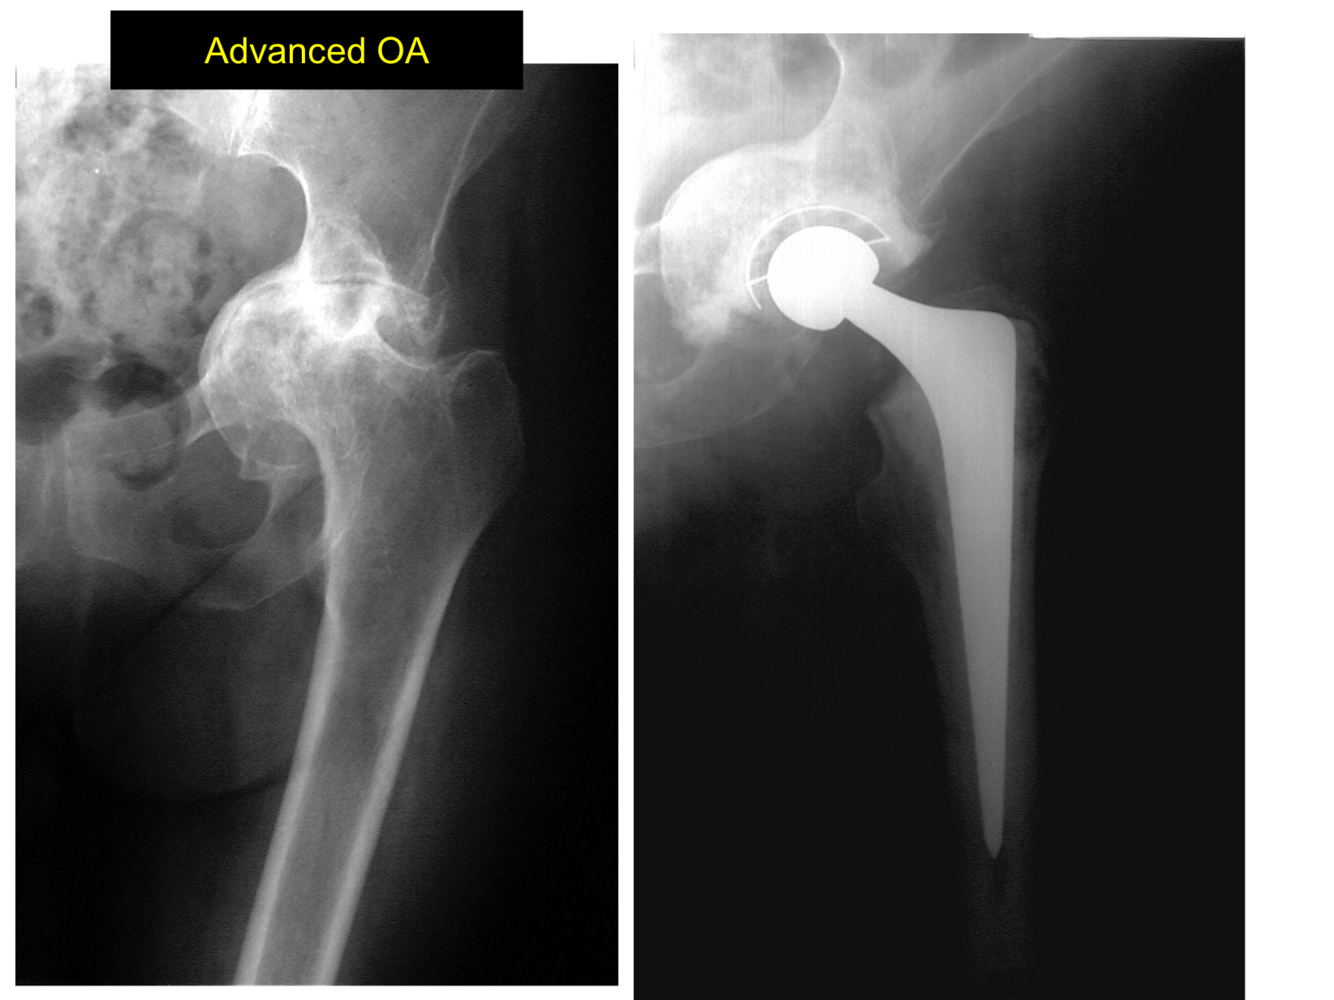

What can be seen on this Xray?

What is the fundamental reason for a hip replacement?

Pain